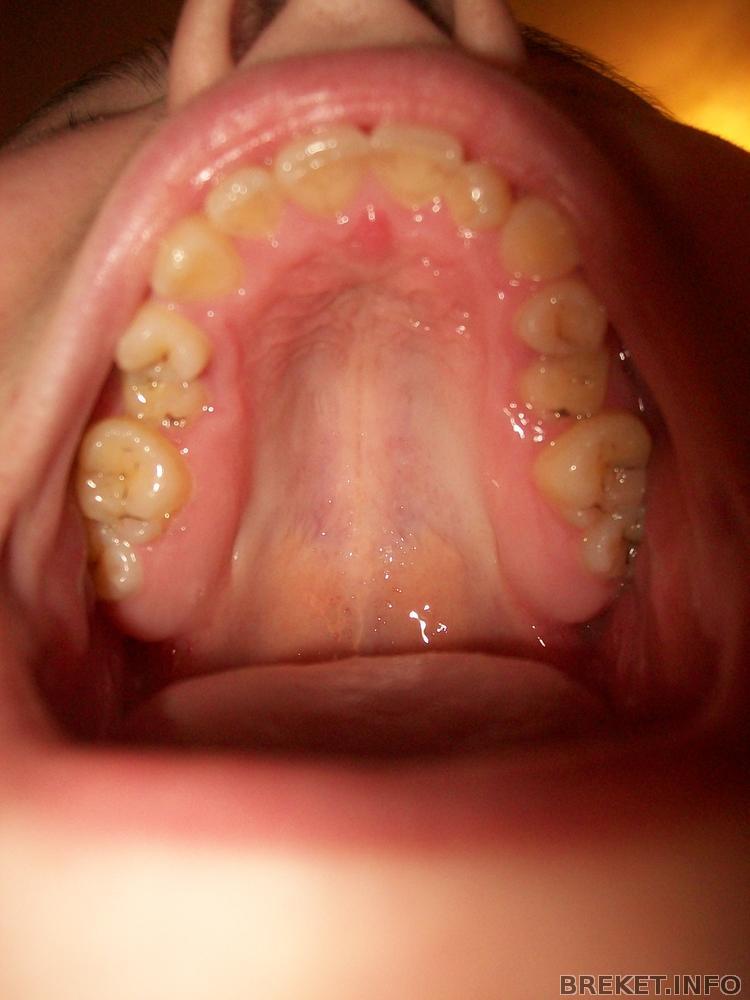

Несоответствие в размерах челюстей

У меня ВЧ маленькая по сравнению к НЧ, в результате чего мезиальный прикус. Мой ортофей сказал, что когда я не сжимаю зубы, то с боку смотрится как правильный прикус, а когда сжимаю, то мезиальный (вот такая ерундень)))) Все это из-за маленьких размеров ВЧ.

Еще плюс ко всему обе 5-ки на ВЧ молочные. Причина этого- полное отсутствие постоянных 5-ых зубов. И молочные не выпадают, орт сказал, что лучше постораться сохранить их ка можно дольше, потом будут имплантанты.

100_6565.jpg